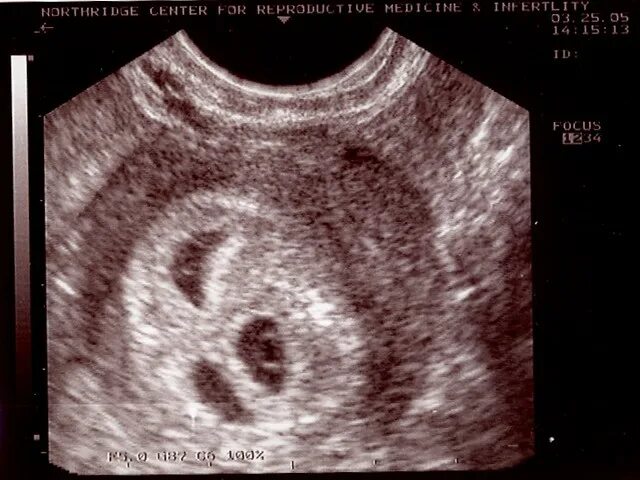

7 неделя февраля